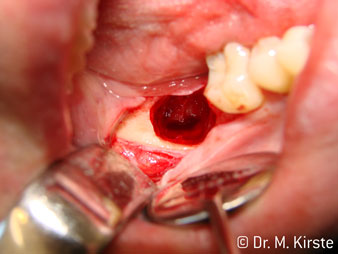

45° ъгъл на наконечника е специално избран поради неговата широка гама от предимства. Колеги, които работят хирургия, и за които този наконечник е главно създаден, скоро ще оценят възможността за ефективна работа в силно ограничени пространства. При екстрахиране на мъдреци, в частност (фиг. 2), няма нужда от голямо разширяване на меката тъкан в областта на бузата (фиг. 3). Дизайнът на главата на наконечника, в съчетание с лекото завъртане на главата по време на препарация, позволява бърза и безопасна работа в ретромоларната област.

Специалният дизайн на лагерите в главата на наконечника гарантира безшумен ход на борера; това прави впечатляващо атравматичен разрез при отделянето на зъба и корена (фиг. 4-9).

Фиг. 2

Фиг. 3